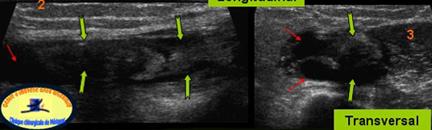

TENOSINOVITA BICEPSULUI

FISURA BICEPSULUI(sageata galbena

INGROSAREA TENDONULUI – SAGEATA PORTOCALIE

EPANSAMENT PERITENDINOS-sag.mov

Hipervascularizatie intrea si peritendinoasa